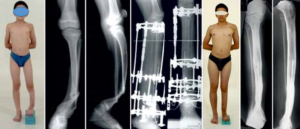

Операция показана детям с 1,5—2-летнего возраста. На первом этапе предусматривается сращение костных фрагментов большеберцовой кости. Концы костных фрагментов большеберцовой кости выделяют поднадкостнично и плотно адаптируют друг к другу боковыми поверхностями на протяжении 3—4 см.

Рис. 6.21. Боковой компрессионный остеосинтез спицами с опорными площадками из кортикальной аллокости при лечении истинной формы врожденного ложного сустава. а — рентгенограммы костей голени до операции; 6 — непосредственно после операции; в — через 2 мес после операции; г — спустя 4 мес после операции — консолидация фрагментов большеберцовой кости.

Через оба фрагмента перпендикулярно продольной оси голени навстречу друг другу проводят две спицы Киршнера с точечными напайками, под основание которых подведены площадки из кортикальной аллокости.

Фиксируют проксимальный и дистальный фрагменты в аппарате Илизарова. Спицами с опорными площадками из кортикальной аллокости осуществляют боковую компрессию (рис. 6.21).

Такая методика позволяет восстановить опорную функцию конечности у всех оперированных больных.